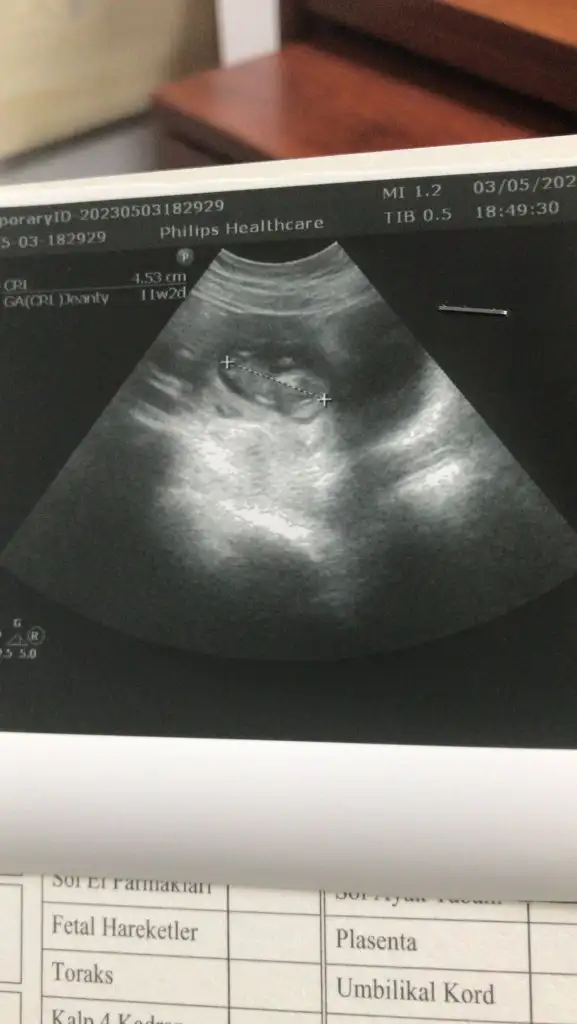

Merhaba arkadaşlar rica etsem ultrasonu değerlendirilmisiniz 11+3 günlük gebeyim

• 9B5A09B3-0B01-4642-A85A-0AFA7AC2511B.webp